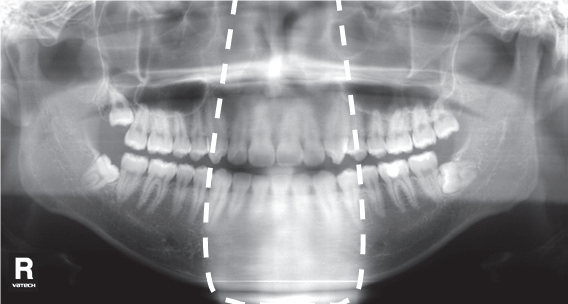

4. Искажения связанные с неправильным положением головы

Рис. 4. Искажения связанные с неправильным положением головы.

Данная ошибка имеет множество вариантов искажений. Это происходит, когда оператор выставил навигационные лазеры неточно, либо пациент смещает голову во время экспозиции.

Что делать:

- Ориентирование головы пациента по вертикальному, горизонтальному и клыковому лазерам обеспечивает четкие снимки и нивелирует подобные искажения.

Лучи должны соответствовать следующим линиям:

1 - медиальная линия лица

2 – линия Франкфурта

3 – средняя линия клыка

Рис. 5. Ориентирование головы пациента по вертикальному, горизонтальному и клыковому лазерам.